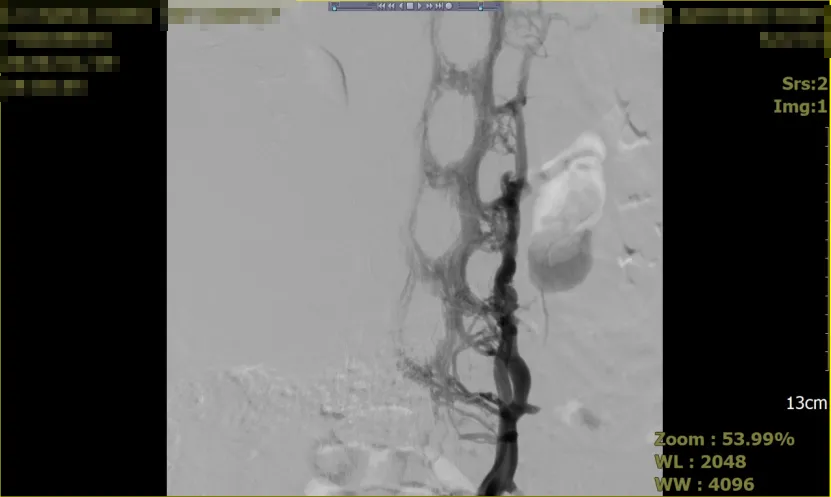

术后影像

在术后查房中(2026年2月2日),患者右腿腿围减小,水肿好转,血栓被清除或被稀释,血流得以恢复,肢体肿胀得到缓解。